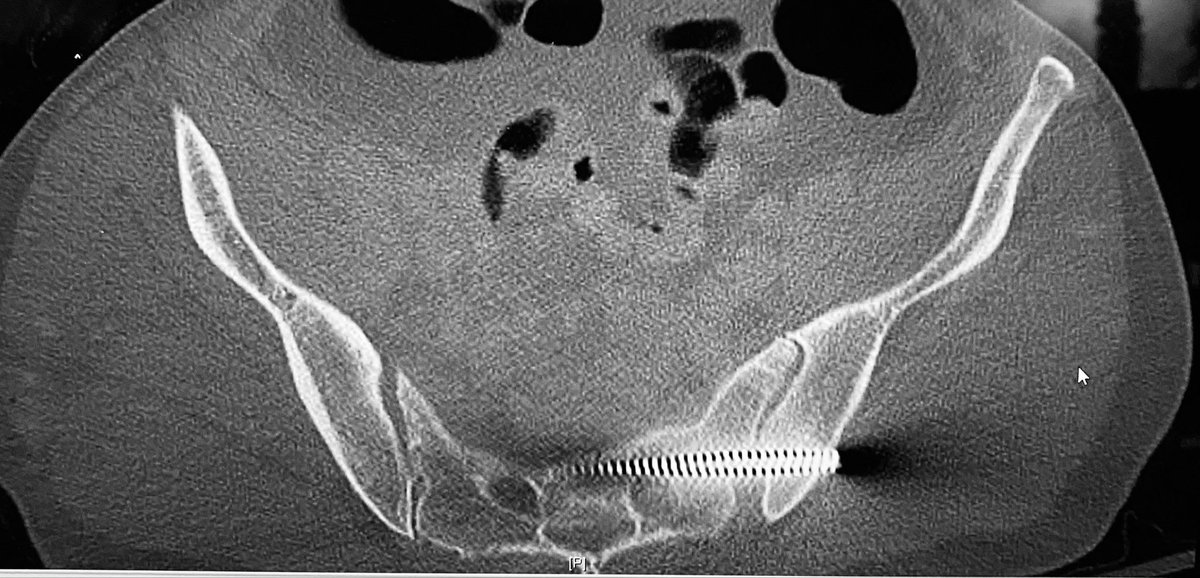

Here is an upper sacral level axial CT image

The posterior pelvis injury is seen as well in this axial CT image at the second sacral level